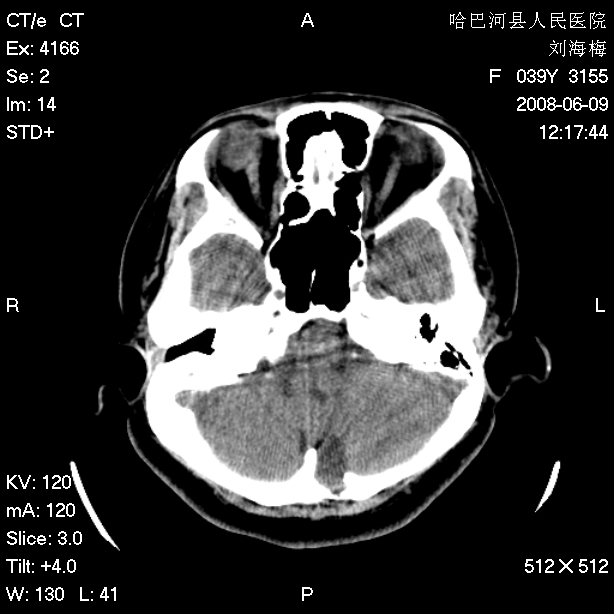

标题: CT13909:F39Y,头痛1年 [打印本页]

标题: CT13909:F39Y,头痛1年

头痛1年

枕骨蛛网膜颗粒压迹。

嗜酸性肉芽肿?骨髓瘤?不像蛛网膜颗粒压迹,太大了,并且有占位效应。

支持枕骨蛛网膜颗粒压迹。头痛与此无关。

2.右中耳乳突应薄扫!

支持蛛网膜颗粒压迹,右中耳乳突应薄扫!

支持枕骨胆脂瘤可能性最大。右侧乳突部密度增高,建议薄扫。